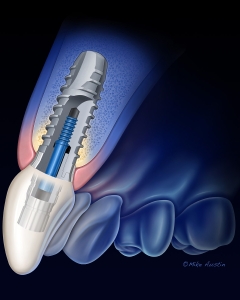

Internal Art Medical Illustration

Blending Art, Anatomy and Science for Creative Visuals

Welcome to my Patient and Professional Marketing page, where I harness the power of anatomical illustrations to educate and empower both patients and medical professionals. My unique approach combines artistry and education to convey complex surgical procedures and the utilization of medical devices in an easily understandable manner.